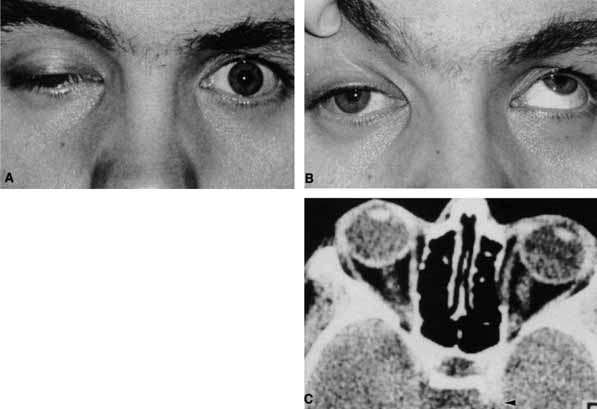

A 30-year-old man noted diplopia and right ptosis for the past month. The patient demonstrated normal vision and symmetric pupils but had a neurogenic ptosis (Fig. 23A) and limited right supraduction (Fig. 23B). Otherwise his extraocular movements were full. CT demonstrated an intracranial aneurysm of the posterior communicating artery aneurysm (Fig. 23C).

Fig. 23 A. A 30-year-old man demonstrates a neurogenic right ptosis. The pupils are symmetric. B. Supraduction of the right eye is limited. Paresis of the superior branch of cranial nerve III was diagnosed. C. Computed tomography (CT) demonstrates a posterior communicating artery aneurysm (arrow).

Anatomically, the third cranial nerve branches into its superior and inferior divisions as it enters the orbit through the superior orbital fissure. Superior branch damage results in ptosis (levator muscle) and decreased supraduction (superior rectus muscle). Inferior branch damage results in decreased adduction (medial rectus), decreased infraduction (inferior rectus), decreased excycloduction (inferior oblique), and a dilated pupil (parasympathetic). Anatomically, a cranial nerve III branch nerve lesion seems to imply an anterior cavernous sinus or orbital apex localization. However, functionally, the third cranial nerve may bifurcate in the intracranial portion of the nerve, so cranial nerve III branch nerve palsies have been demonstrated with intracranial lesions. The localizing finding of a cranial nerve III branch nerve lesion is therefore not absolute (see Fig. 23).46